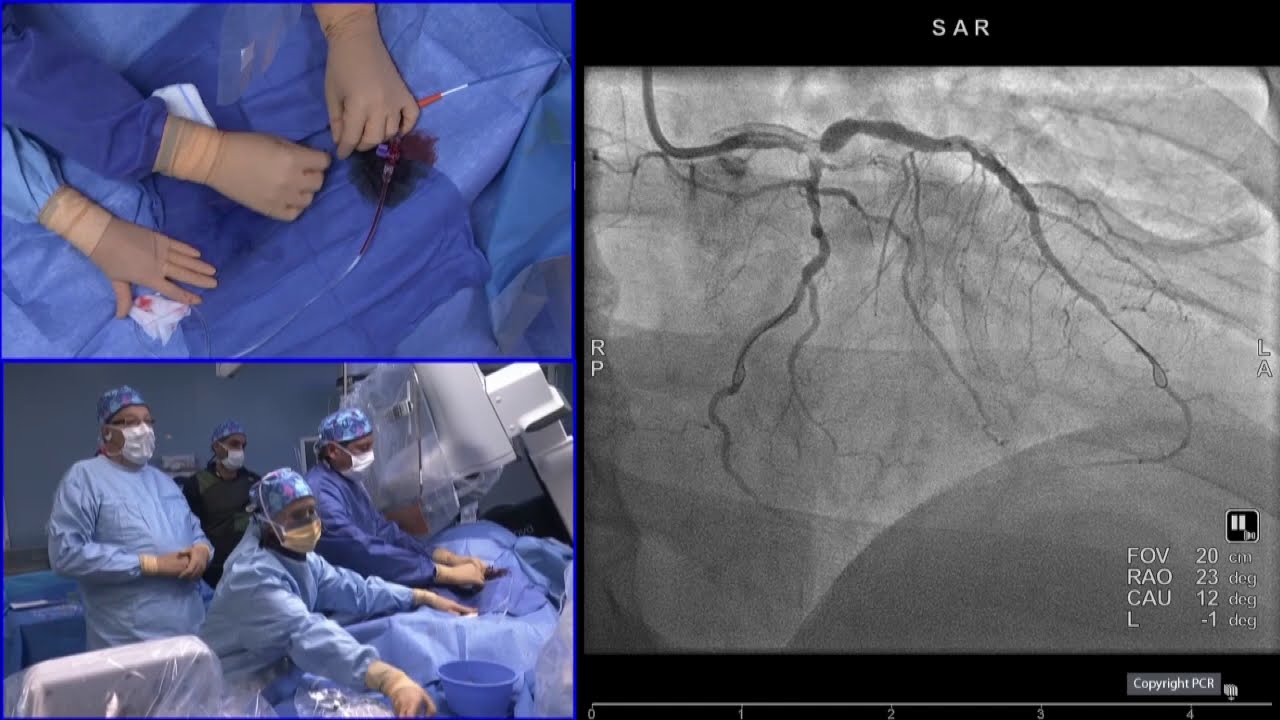

Complex PCI in high bleeding risk patients

interventional cardiologycardiologycardiovascularinterventional cardiovascular medecineEuroPCRPCRonlinePCR onlineLeft mainLMMultivessel diseaseMVD high bleeding risk patientsPCIantithrombotic strategyHBRDES

Chairpersons: T. Cuisset, M. Valgimigli

Learning Objectives:

To identify HBR patients requiring adjusted antithrombotic strategy

To tailor PCI strategies to specific HBR patient for drug-device synergy

To reflect on the selection of new DES in HBR patient

This webcast is supported by Terumo and was filmed at #EuroPCR 2019. View more videos and webcasts here: https://www.pcronline.com/Cases-resou...